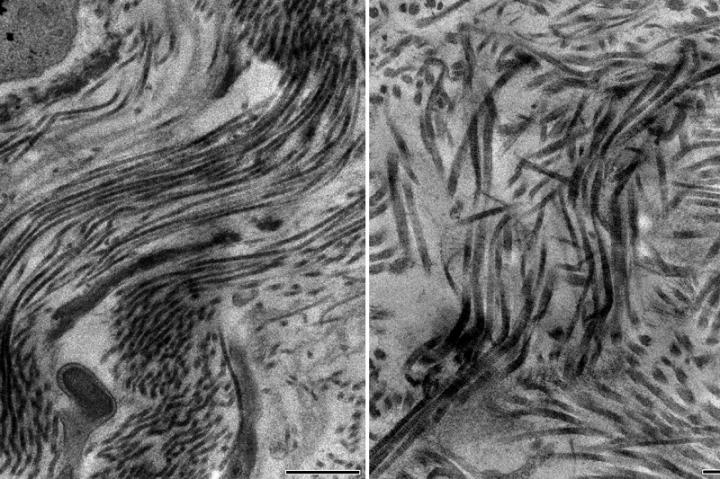

image: Electron microscopy images showing a healthy scar containing collagen type 5 with scar fibers smoothly arranged in parallel (left) and unhealthy scar containing no collagen type 5 with a disorganized architecture with disarray of scar fibers (right).

Digging deeper, Deb and his collaborators from the Geffen School of Medicine, the California NanoSystems Institute at UCLA and the UCLA Division of Life Sciences found that type 5 collagen was regulating the stiffness of scar tissue. Without it, the scar tissue was less stiff and therefore prone to expansion from the force of the blood within the heart.